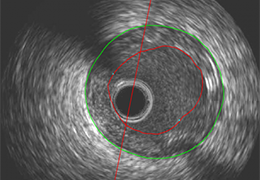

Performs 3D reconstruction and volume rendering.

Multi-planar slicing.

Oblique slicing.